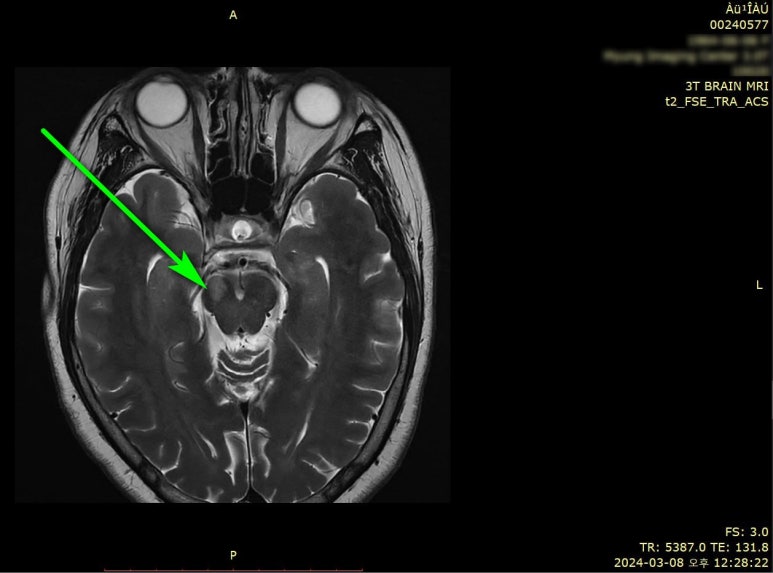

Brain MRI상 뇌경색 진단

3T Brain MRI검사 결과

뇌로 가는 혈관이 막힌

이 발견되었습니다.

우측 뇌교 상부(Right pons upper side)

급성 뇌경색(acute infarction)으로진단되셨고요.

영상의학과 핫라인을 통해

대학병원 응급실로 전원하였습니다.

2주간 입원하여

항응고 치료 후

큰 후유증 없이

퇴원하셨고요.